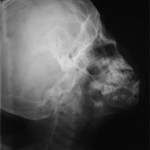

2. Lateral Oblique: Excellent for viewing the mandibular body and ramus.

TO VIEW BODY OF MANDIBLE

-views premolar, molar and inferior border of the mandible; broader than PA’s

-example: Body Of Left Mandible [right to left]

x-ray tube [aimed under right side of mandible]  head tilted to left

 cassette held against side of face by patient parallel to border of mandible and extending 2 cm below it [centered on 1st molar]; 65 kVp, 10 mA

TO VIEW RAMUS OF MANDIBLE

-views ramus from the angle of the mandible to the condyle; useful for ¬ /  3rds

-example: Ramus of Left mandible [right to left]

x-ray tube [aimed under right side of mandible]  head tilted to left until a line from the right angle of the mandible to the left condyle is parallel to the deck

 protrude the mandible. This keeps the spine out of the view.

 cassette held against side of face [ramus] by patient and extending 2 cm below the inferior border of the mandible; 65 kVp, 10 mA